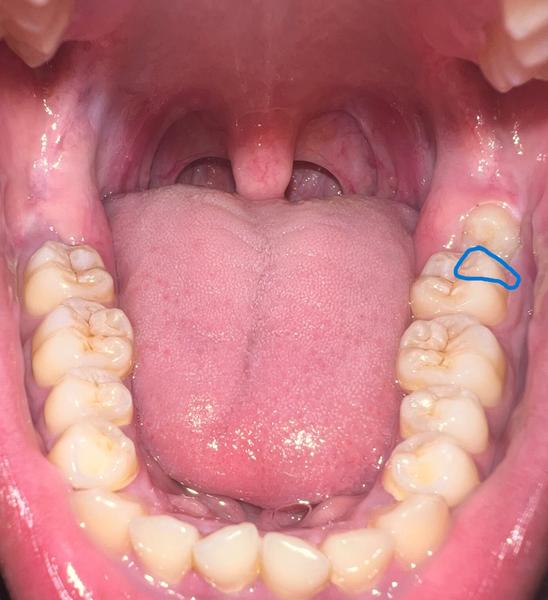

ปรึกษาเรื่อง ทำฟัน ครับ

เมื่อ 2 อาทิตย์ก่อน ฟันกรามใหญ่ด้านในของผมแตกไป 1 ใน 4 ส่วน ตามรูปตัวอย่างที่ผมวงสีน้ำเงินคือส่วนที่แตก (รูปตัวอย่างหามาจากในเน็ตครับ)

ผมเลยคุยกับหมอ เบื้องต้นทำการอุดฟันที่เป็นรูก่อน ตอนนี้ก็อุดเรียบร้อยแล้ว และหมอบอกว่า เหมือนว่าน่าจะมีรอยลึกไปถึงรากฟัน ยังไงก็ควรมารักษารากฟันและครอบฟันนะ แต่ต้องผ่าฟันคุดออกก่อน (เหมือนในรูปเลยครับ ฟันคุดอยู่ติดฟันกรามแบบในรูปเลย) ผ่าฟันคุดประมาณ 3,500 - 4,000 แล้วแต่เคส เบื้องต้นผมรับทราบ และบอกว่าถ้าพร้อมจะมาผ่าออกครับ